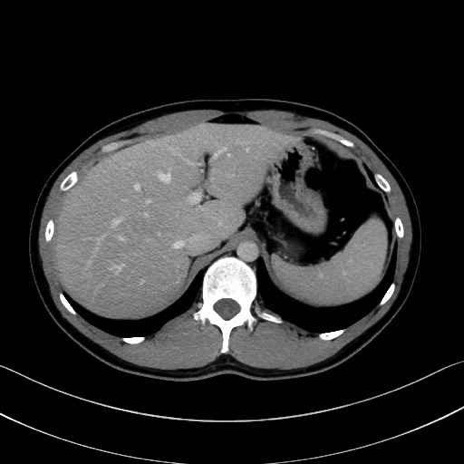

脾動脈の画像解剖

■起始:典型的には腹腔動脈幹(celiac trunk)から左胃動脈・総肝動脈とともに三分岐し、脾動脈は左後上方へ向かう。

■走行:膵上縁または膵実質背側を蛇行しながら左方へ進み、膵尾部近傍で脾門へ至る。蛇行の程度は個体差が大きい。

■終枝:脾門部で複数の終末枝に分かれ、上極・下極枝や脾門枝群を形成する。胃短動脈群や左胃大網動脈はしばしば脾動脈から分岐する。